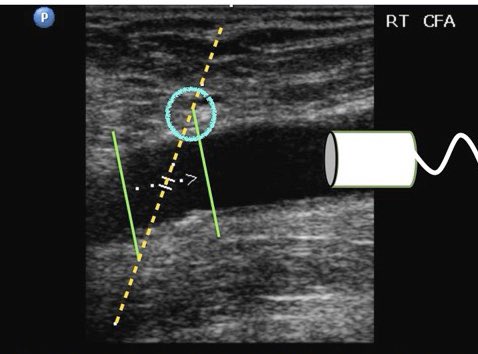

طيب لو فرضنا ان الـ box مو موجود نعرف مكان البروب عن طريق

" simple volume and angel cursor “ نرسم خطين تخيلين ( الخط الي يلمس الـ beam path من "الجهه العلويه " راح يكون البروب بنفس الجهه هذي )

مثال : لو الخط الي رسمناه لامس الـ beam path من اليمين راح يكون البروب يمين والعكس

طبق المعايير الي فوق على هالصورتين وبتعرف هل الاتجاه صحيح او لا